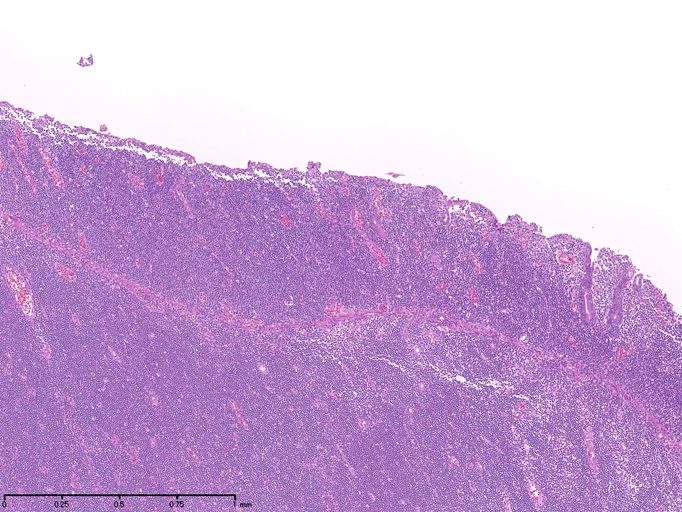

腫瘍細胞は腸管全層に密に浸潤している。粘膜表面は上皮が消失しびらんを形成。(Fig.1), 高倍率では中型, medium sized(組織球の核とほぼ同じサイズ)の類円形核をもつ比較的淡明な細胞質の異型リンパ球様細胞が密にmonotonousな増殖を示している。(Fig.2,3)

粘膜固有層には腫瘍細胞が充満し腺窩基底膜側より陰窩内に進入してIntraepithelial lymphocyte(IEL)の上皮浸潤を模倣する特徴的な蚕食像を示している。(Fig.4)

Fig.1Fig.2Fig.3Fig.4